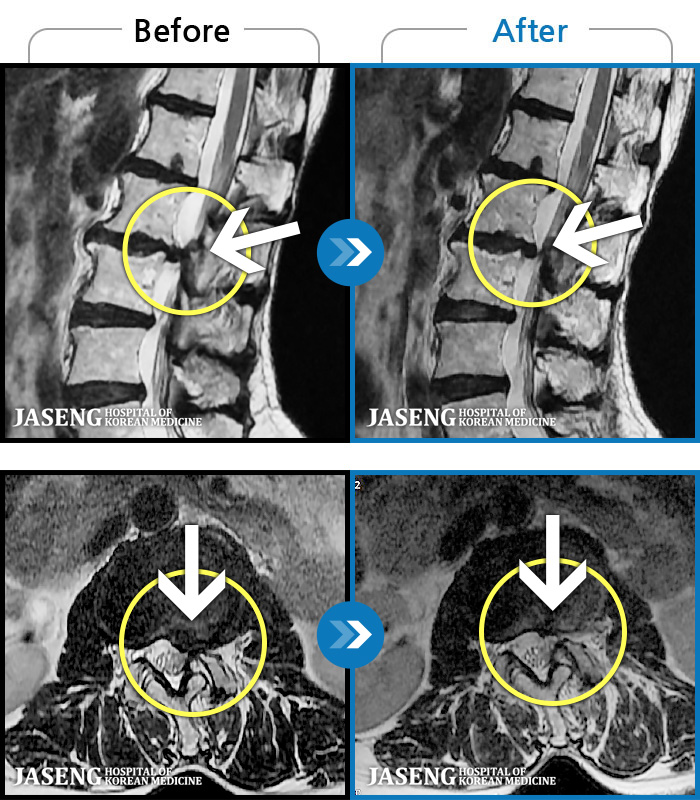

허리디스크

해운대 · 김상돈 원장

허리가 찌릿찌릿하고 찢어질 것 같은 통증

촬영시기

2024.01.08 ~ 2025.08.12

2025.08.29